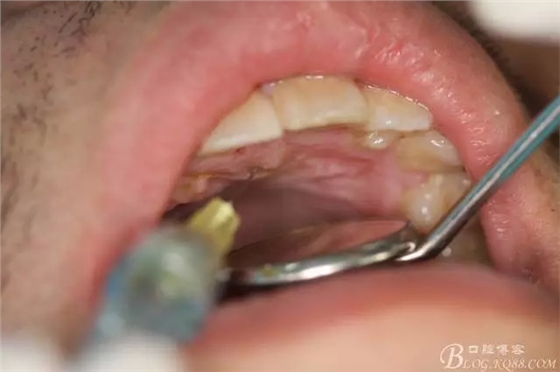

圖1.術(shù)前患者口內(nèi)影像檢查:右上乳Ⅱ滯留,12、13未萌出。粘膜表面觸診有骨性隆起并且凹凸不規(guī)則。

圖3.唇、腭側(cè)局部浸潤麻醉